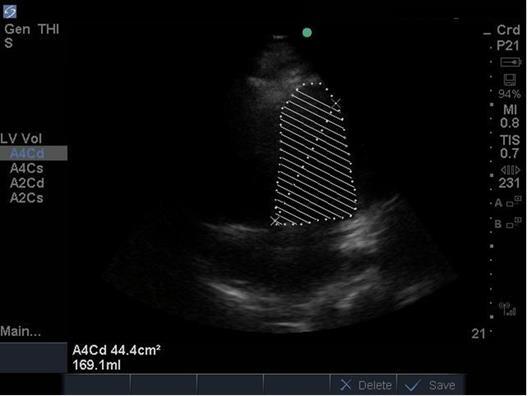

Heart Ejection Fraction (EF) 1 Image